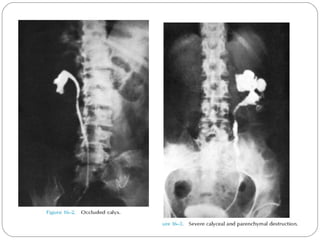

GU Tb-IVU

The most common findings being

hydrocalycosis,hydronephrosis, or hydroureter due to

stricture formation .

 Early signs include the moth-eaten appearance of

calyceal erosion and papillary irregularity- signs are

best seen on early excretory films.

Cavitary lesions communicating with the collecting

system are characteristic of TB.

 These lesions eventually enlarge as parenchymal

destruction ensues.

Fibrotic distortion of the collecting system and ureter

is also seen.

Calyceal obliteration and amputation, hydrocalycosis,

segmental or total hydronephrosis, and a shriveled

reduced capacity renal pelvis may all be signs of renal

tuberculosis

Scarring and angulation of the ureteropelvic junction

(UPJ) may also occur, the so-called “Kerr’s kink” .